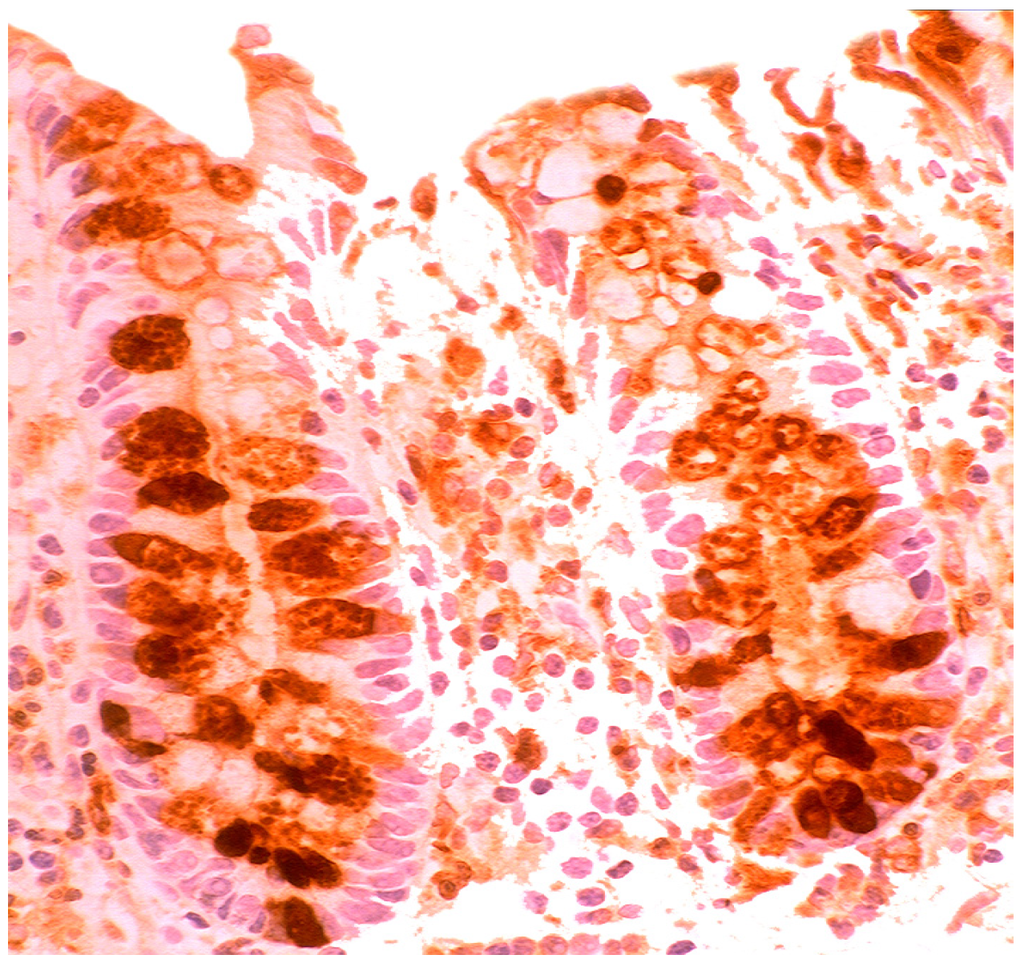

Barrett’s mucosa (intestinal phenotype) showing lysozyme up-regulation, particularly in the luminal epithelial border and in goblet cells (lysozyme immunostain, ×40).

When compared to controls, lysozyme was up-regulated in all three Barrett’s mucosal phenotypes [24]. In some goblet cells, lysozyme was slightly expressed. This phenomenon might be due to a prior goblet cells-discharge of lysozyme-rich intracellular mucus into the lumen (Figure 3). Lysozyme was not expressed in parietal (oxyntic) cells, neither in Barrett’s oesophagus (Figure 4), nor in controls [24].